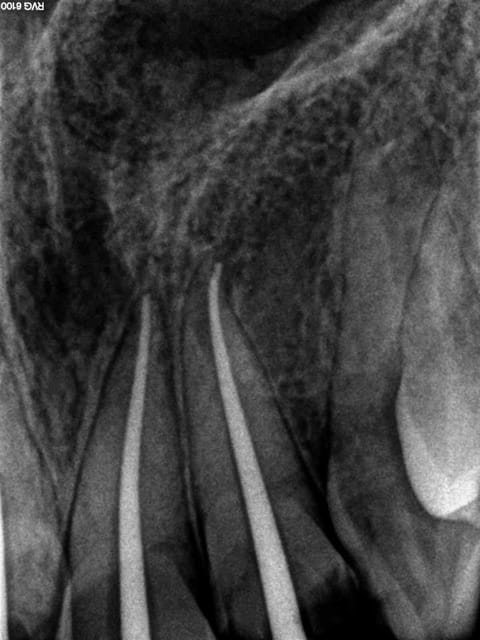

Et 1 h plus tard, fin du massacre conventionnel, no post no crown !.-)))

3 cvcjke - Eugenol

1 guqoin - Eugenol

2 v4h37g - Eugenol

4 s7ibd3 - Eugenol

5 ikfkap - Eugenol